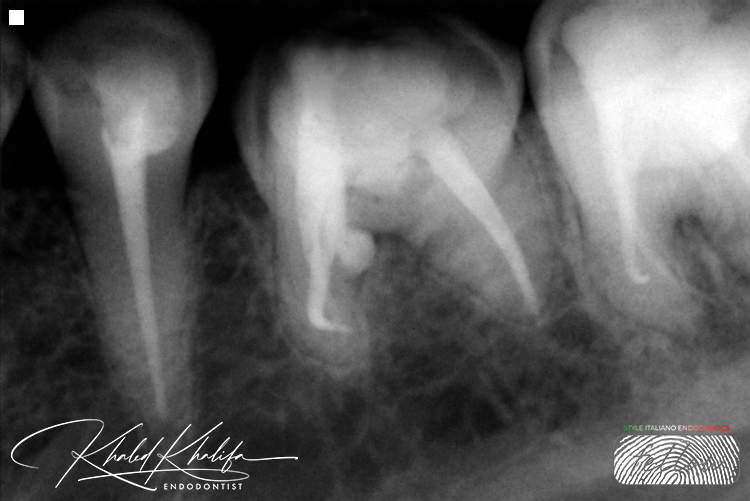

Unfortunately, in this case as you can see, the previous doctor tried to retrieve/bypass the file before referring the case as seen in the first 2 photos they made a perforation above the broken file in inner wall.

Broken File Retrieval + Managment of Acute Curve + Sealing Perforation and Coronal part of the root with Bioceramic Material.